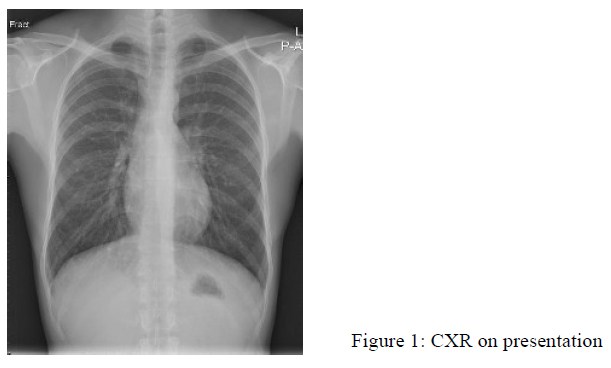

Physical examinations were mostly unremarkable. The blood pressure was normal. Initial blood tests showed Hb 19.5g/dL, Hct 0.56L/L, white blood cell 5.5 x10^9/L, platelet 211 x10^9/L with normal liver and renal function tests. His CXR on presentation was shown in Fig. 1.

The chest radiograph is abnormal in the majority of patients with symptoms attributable to PAVM. The classic chest radiograph appearance of a PAVM is that of a round or oval mass of uniform density, frequently lobulated but sharply defined, more commonly in the lower lobes, and ranging from 1 to 5 cm in diameter. Patients who have multiple PAVM usually have 2 to 8 lesions. Hemorrhage into contiguous parenchyma, or atelectasis may obscure the PAVM shadows in chest radiograph. If patients have microvascular telangiectases, chest radiographs can be normal, or there may be just a vague increase in pulmonary vascular markings at the bases. Sometimes, the chest shadows of PAVM may come and go1.